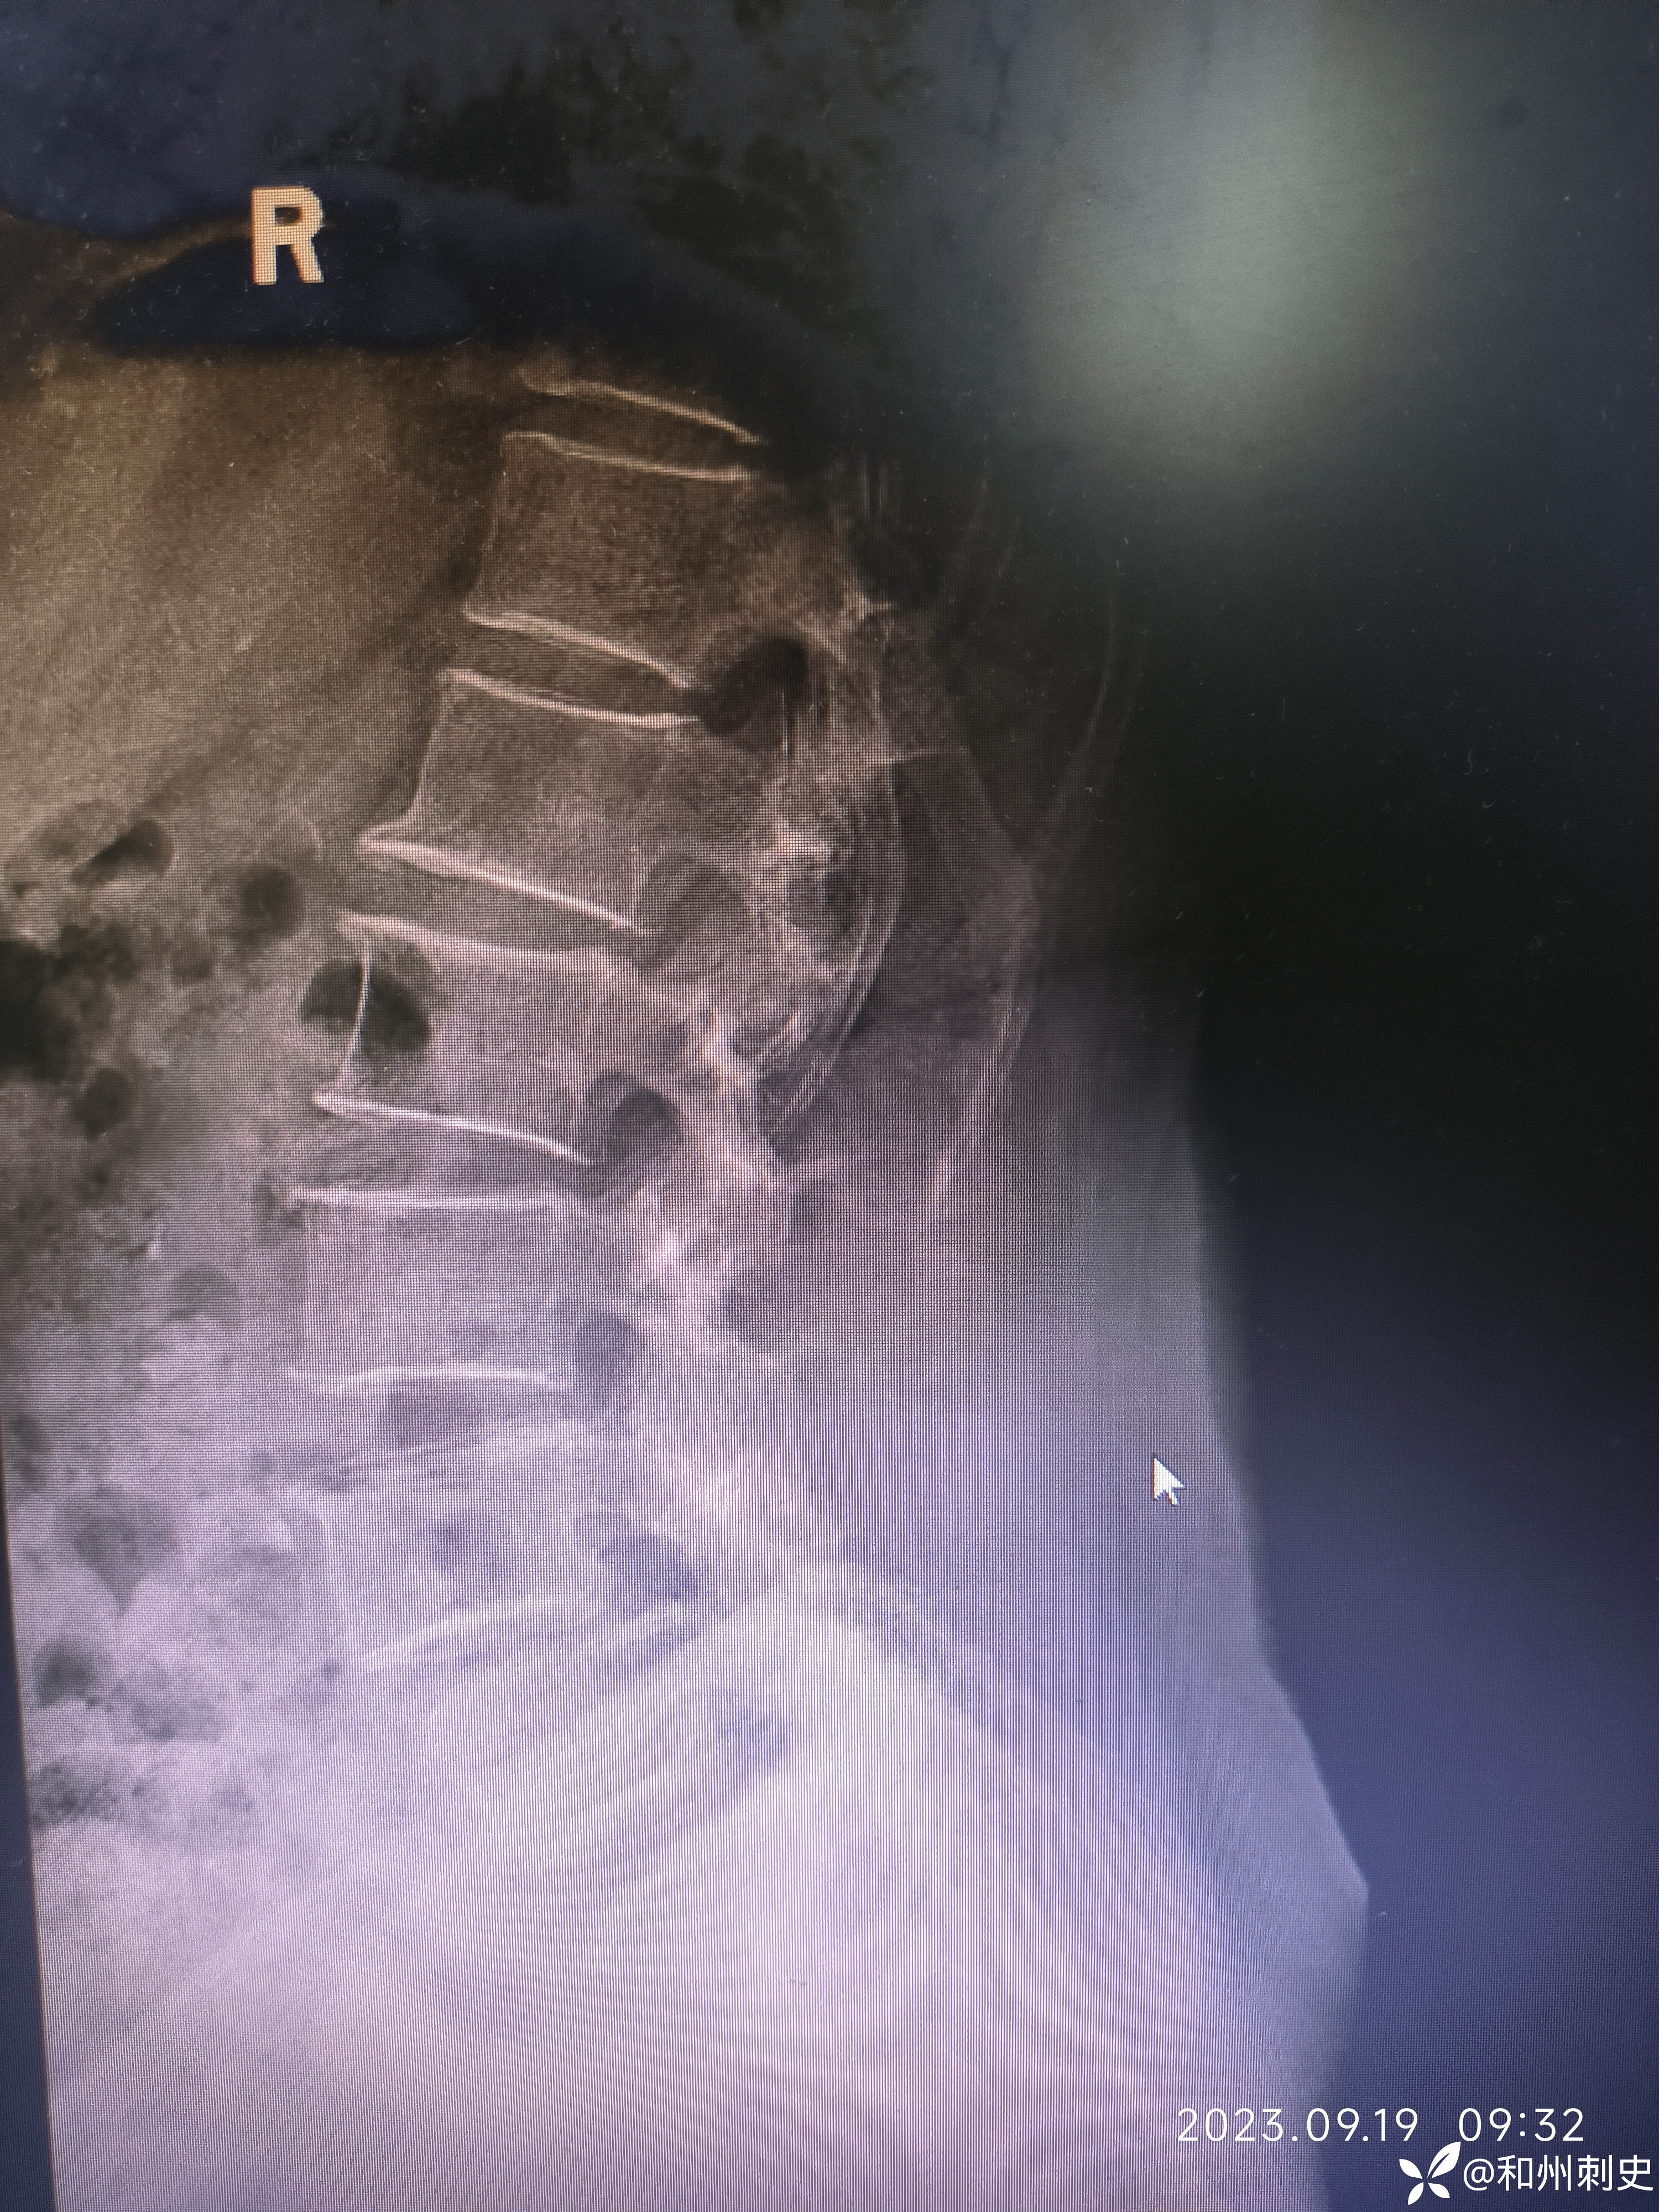

腰椎滑脱、椎管狭窄症患者,术后膝关节疼痛缓解、伸直改善。

老年女性,腰痛多年,逐渐出现右臀部疼痛,右膝疼痛,伸直受限。查体:下腰椎棘突压痛,右膝伸直差15度,被动伸直受限,疼痛,被动屈曲疼痛。

做了腰4/5减压复位融合内固定手术,术后右膝关节疼痛明显减轻,也基本伸直了,对此有点不明白原因。请教各位老师。